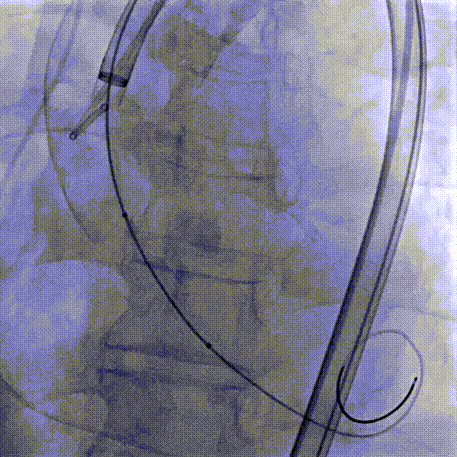

Step 8.最终造影:真实瓣环下方3mm标准位,完全同轴,轻微反流,猪尾撤出后反流完全消失

Step 9.CuspOverlap体位验证缘对缘对齐,挂钩位于最右方,基本避开冠脉开口

Step 10.验证器械同轴性,完全同轴